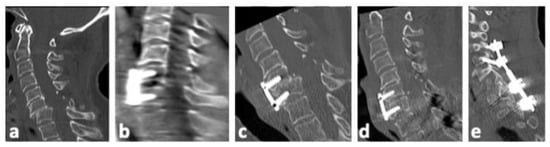

| No | Sex | Age | Level | Injury Type | Primary Treatment | Therapy of Secondary Dislocation |

|---|---|---|---|---|---|---|

| 1 | f | 91 | C6/7 | B2 | ACDF C6/7 with plate and iliac crest graft | Posterior instrumentation C5/6/7/Th1 |

| 2 | f | 74 | C5/6 | B2 | ACDF C5/6 with plate and iliac crest graft | Removal of plate and ACDF C5/6/7 with plate |

| 3 | m | 78 | C6/7 | B3 | Posterior instrumentation C3/4 to C6/7 andAnterior fixation C5 to C7 with plate | Posterior instrumentation C3/4/5/6/7Anterior fixation C5 to C7 with plate |

| 4 | m | 82 | C5/6 | B3 | ACDF C5/6 with plate and iliac crest graft | Posterior instrumentation C3/4/5/6/7 and ACDF C4/5/6/7 with plate and intervertebral cages |

| 5 | m | 66 | C6/7 | B3 | ACDF C5/6/7 with plate and iliac crest grafts | Halo fixator |

| 6 | f | 80 | C6/7 | C | ACDF C6/7 with plate and allogenous bone graft | Posterior instrumentation C4/5 to Th1/2 |

| 7 | f | 70 | C6/7 | C | ACDF C6/7 with plate and iliac crest graft | Posterior instrumentation C3/4/5 to Th1/2 |

| 8 | m | 68 | C6/7 | C | ACDF C6/7 with plate and iliac crest graft | Posterior instrumentation C6/7/Th1/2 |

| 9 | f | 74 | C6/7 | C | ACDF C5/6/7 with plate and intervertebral cages | Posterior instrumentation C5/6/7/Th1 |

| 10 | m | 79 | C6/7 | C | ACDF C6/7 with plate and iliac crest graft | Posterior instrumentation recommended; patient refused |

| 11 | f | 67 | C5/6 | C | ACDF C5/6 with plate and intervertebral cage | Posterior instrumentation C4/5/6/7 |